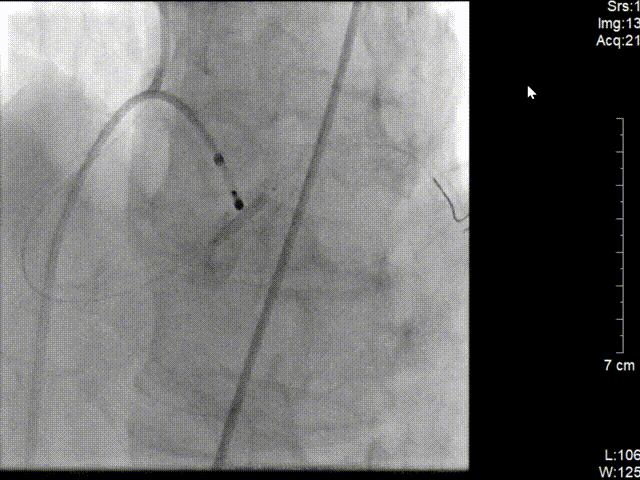

C.立即穿刺股静脉行临时起搏器植入;

D. 时间急迫,穿刺股动脉建鞘行急诊PCI;

E. 为节省时间,选择6F JR4.0指引导管进行冠脉造影,提示右冠近段完全闭塞,通过JR4.0行急诊PCI,迅速开通闭塞右冠,于右冠远段、近段各植入药物支架1枚。